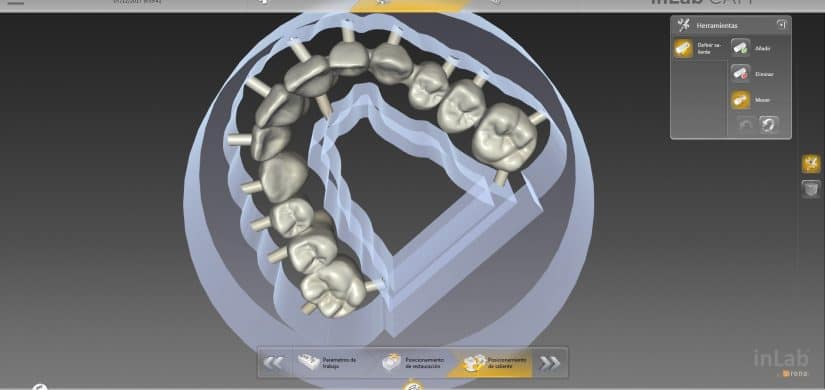

Tecnología de punta

- Radiografías digitales y tomografía 3D: planificación precisa del implante.

- Software de diseño de sonrisa (DSD): visualización del resultado antes del tratamiento.